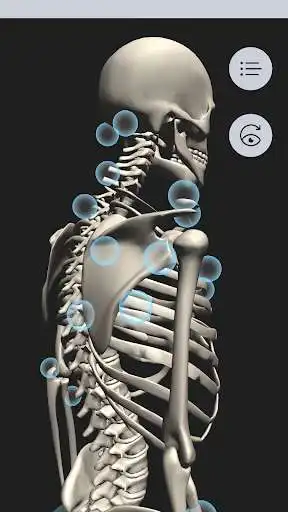

OT Kinesiology Pro Consult is a resource to learn how to correctly and accurately measure joint range of motion.See the movement being measured in clinic, highlighting goniometer placement and the prime muscles involved in an animated 3D skeleton.

Tap joints on the skeleton to view flexion contentMuscles associated with each flexion

Anatomical reference and clinical video examples for each flexion